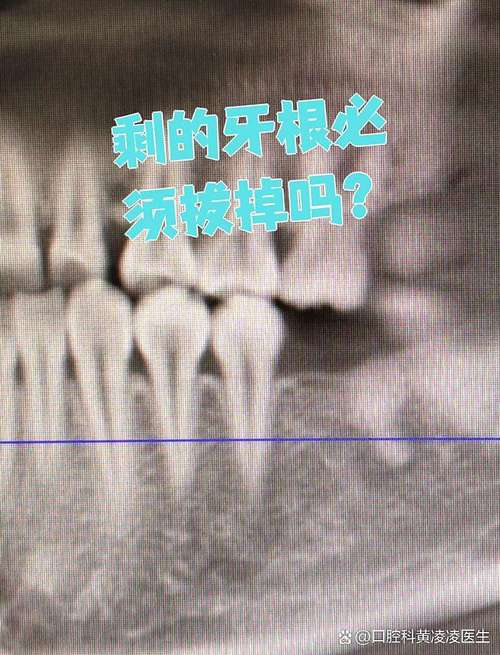

- X光片(根尖片、曲面断层片、CBCT): 评估牙根长度、形态、龋坏范围、根尖病变、牙槽骨状况、邻牙情况等。